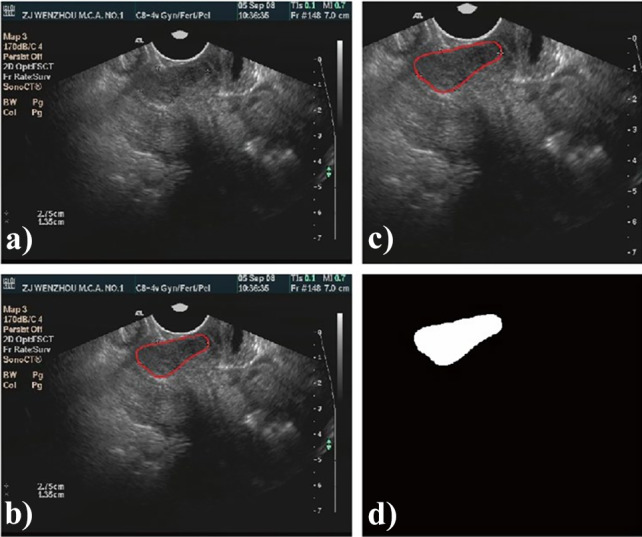

In order to meet the size requirement of automatic segmentation algorithm, image clipping was performed on each image set, and the center of clipping box was shifted randomly in all directions to make the training model robust [19]. The clipping box should be within the boundary of image and covers the tumor. A typical image preprocessing is shown in Fig. 2.

Fig. 2.

A typical preprocessing for automatic segmentation modeling with ultrasound images: a original ultrasound image; b manually contoured target area; c image after clipping; d the mask of cervical cancer target